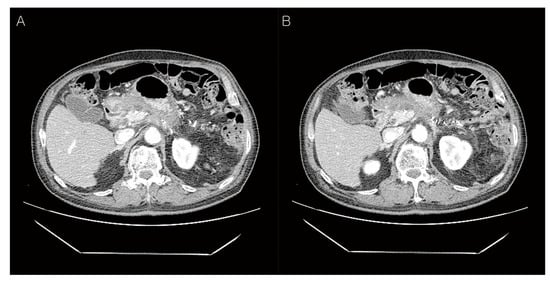

Figure 1. Preoperative abdominal computed tomography (CT) findings. A 72-year-old man presented with a pancreatic mass on abdominal CT. However, he had no other symptoms of jaundice, abdominal pain, or weight loss. On physical examination, the liver and spleen were not enlarged and the vital signs were stable. He was diagnosed with hepatitis B and C 30 and 10 years ago and had received anti-viral treatment (Table 1). Subsequently, he was diagnosed with hepatocellular carcinoma in segment 7 and treated with radiofrequency ablation (RFA). Eight years later, an additional RFA treatment was performed for the newly developed hepatic mass in segment 8 (Table 1). The laboratory data were as follows: total protein 6.7 g/dL (normal: 6.6–8.7 g/dL), albumin 4.0 g/dL (normal: 3.5–5.2 g/dL), total bilirubin 0.37 mg/dL (normal: <1.2 mg/dL), direct bilirubin 0.2 mg/dL (normal: 0.01–0.3 mg/dL), serum AST 17 U/L (normal: ≤40 U/L), ALT 19 U/L (normal: ≤41 U/L), serum CEA 2.3 ng/mL (normal: 0–7.0 ng/mL), serum CA19-9 121.0 U/mL (normal: 0–37.0 U/mL), amylase 98 U/L (normal: 28–110 U/L), lipase 91 U/L (13–60 U/L), BUN 16.3 mg/dL (normal: 6–20 mg/dL), creatinine 0.58 mg/dL (normal: 0.7–1.2 mg/dL). Follow-up contrast-enhanced abdominal CT showed an approx. 4.0 cm-sized hypodense mass in the distal body and tail of the pancreas with an irregular margin (A). The upstream pancreatic duct dilatation was also detected (B). Hence, the patient’s condition was diagnosed as pancreatic ductal adenocarcinoma preoperatively.